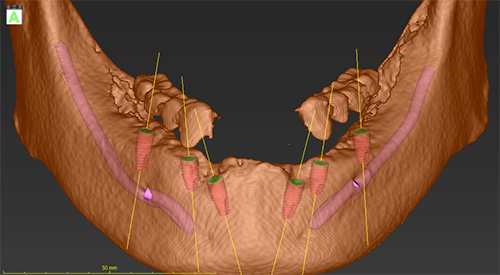

高精度CTとインプラントシミュレーションを用いた精密なインプラント治療

インプラント治療で大切なのは診断です。顎の骨や神経、血管の位置を正確に、そして詳細に把握できる高精度CTの3次元立体画像を活用して、的確な診断を行います。詳細なデータをもとに、専用ソフト上でシミュレーションを行い、0.数ミリ単位でインプラントの位置を確認します。

必要があれば、そのデータから位置がずれないようにインプラントガイドを作成することも可能です。

インプラントガイドを使用することにより、シミュレーションで想定した位置と同じ位置にインプラント埋入が可能になります。

シミュレーション画像